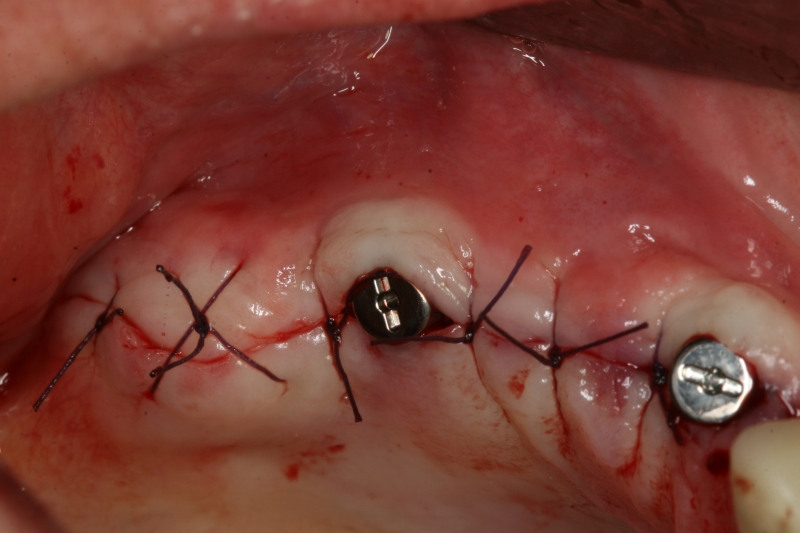

Implant insertion in atrophic alveolar ridge